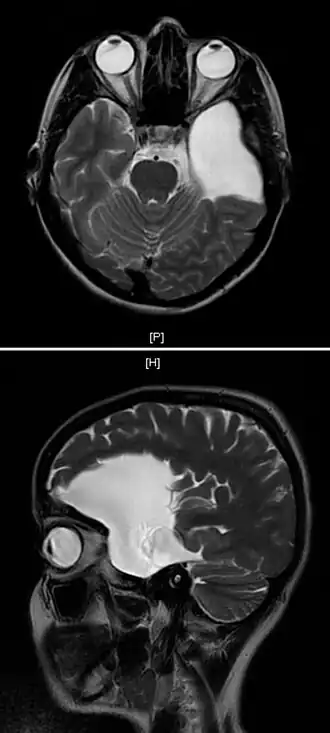

| Uma ressonância magnética de uma mulher de 25 anos com um cisto aracnoide no lobo frontal esquerdo. | |